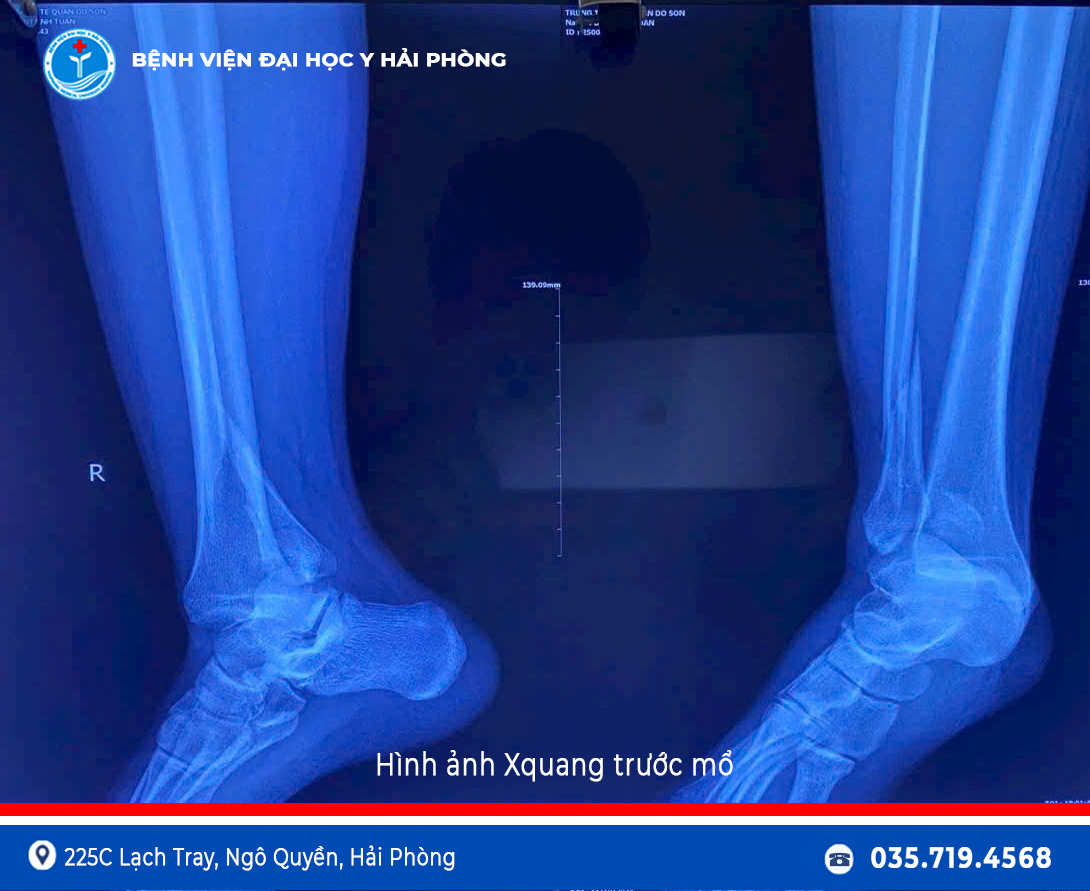

Vừa qua, Bệnh viện Đa khoa Đồ Sơn đã tiếp nhận một bệnh nhân nam 17 tuổi bị chấn thương vùng cổ chân phải sau khi đá bóng. Bệnh nhân nhập viện trong tình trạng đau nhiều, sưng nề và hạn chế vận động cổ chân phải.

Kết quả hội chẩn cho thấy bệnh nhân bị gãy kín đầu dưới xương mác, gãy kín mắt cá sau và trật khớp cổ chân phải, chỉ định phẫu thuật kết hợp xương và nắn chỉnh trật khớp sớm để đảm bảo phục hồi chức năng vận động.